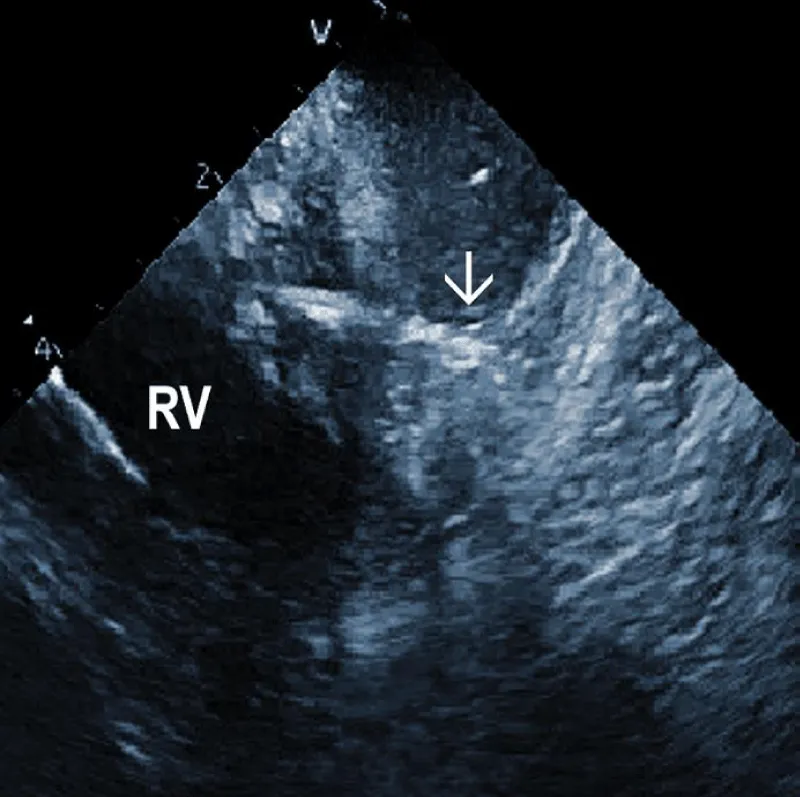

Additional echocardiographic findings: ICE can detect less frequent but important abnormalities, which may relate to TLE or subsequent lead implant. An example could be complete obstruction of the superior vena cava or the brachiocephalic vein. An additional curious finding which can be observed by ICE, is the deformation of the right ventricle during traction on the lead, often leading to hypotension [30]. The ability to visualize the lead-tissue interface during extraction (Figure 5B) and assess lead binding sites allows the operator to continuously evaluate the response to extraction maneuvers. Monitoring the progression and alignment of the laser extraction sheath with the lead is another potential utility of ICE (Figure 5C).

Figure 5B: Traction on the RV wall at the site of attachment of the ICD lead (arrow).